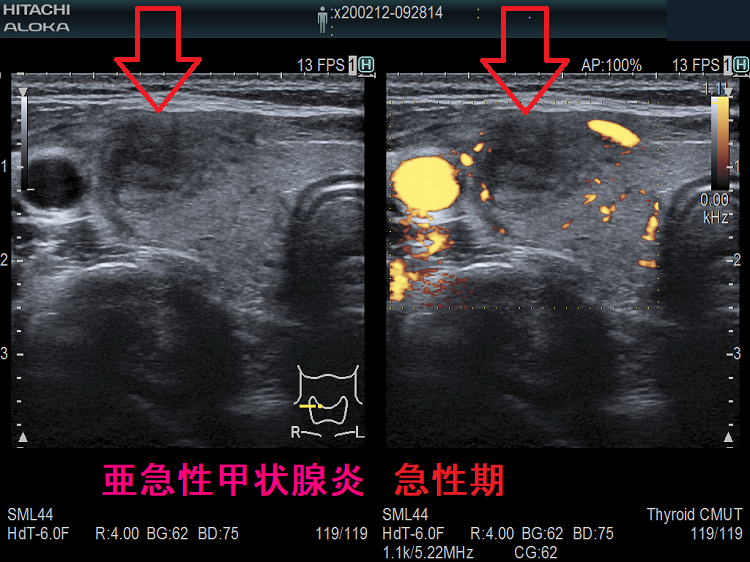

下は亜急性甲状腺炎の超音波(エコー)画像で、炎症の強い部分は黒く、エラストグラフィーでは青くなります。